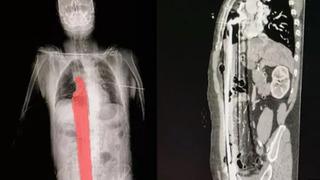

Korkunç olay! İskeleden düşen adamın gövdesinin tamamına demir çubuk saplandı... İç organları delindi

Brezilya'da 57 yaşında bir adam, iş yerinde düştükten sonra iç organlarının birçoğunu delen keskin bir çubuğa saplandı. Demir çubuk tesadüf eseri kalbini kıl payı sıyırınca 57 yaşındaki adam hayatta kalmayı başardı.